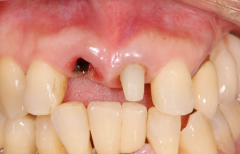

自己採血してCGF&AFGを再生に使用した症例

<治療前>

上顎前歯部が崩壊して残すことが出来ない状態になっている。

<治療後>

抜歯した部位にインプラントを埋入し半年かけて

歯肉と歯槽骨を再生させて審美的な歯(セラミック冠)を入れました。